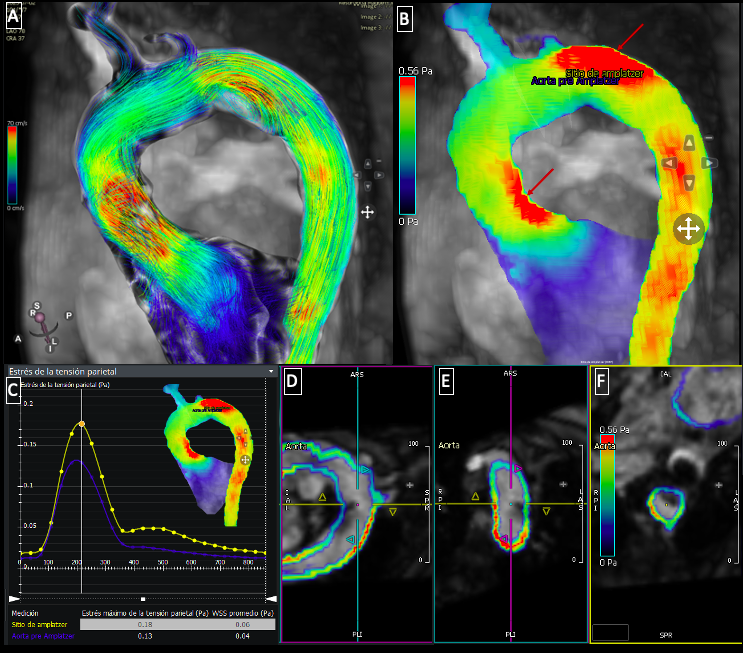

Fig. 3 4D Flow in the aorta: A) Pathline visualization demostrating flow acceleration in the ascending aorta and turbulent flow at the site of device protusion. B) Regions of increased wall shear stress (red arrows). C) Quantification in pascals (Pa) comparing wall shear stress before the device and at the device site. D-F) Multiplanar reconstructions illustrating the location and extent of the device protrusion within the aortic lumen.